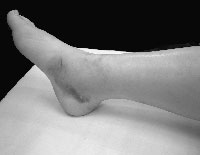

現症:歩行不能、加重痛、軸圧痛、限局性局所圧痛、足底からの叩打痛、変形、腫脹

右下腿内足方向よりの写真。内果下方に内出血を認める。 |

左下腿外側方向よりの写真。外果下方に内出血を認める。 |